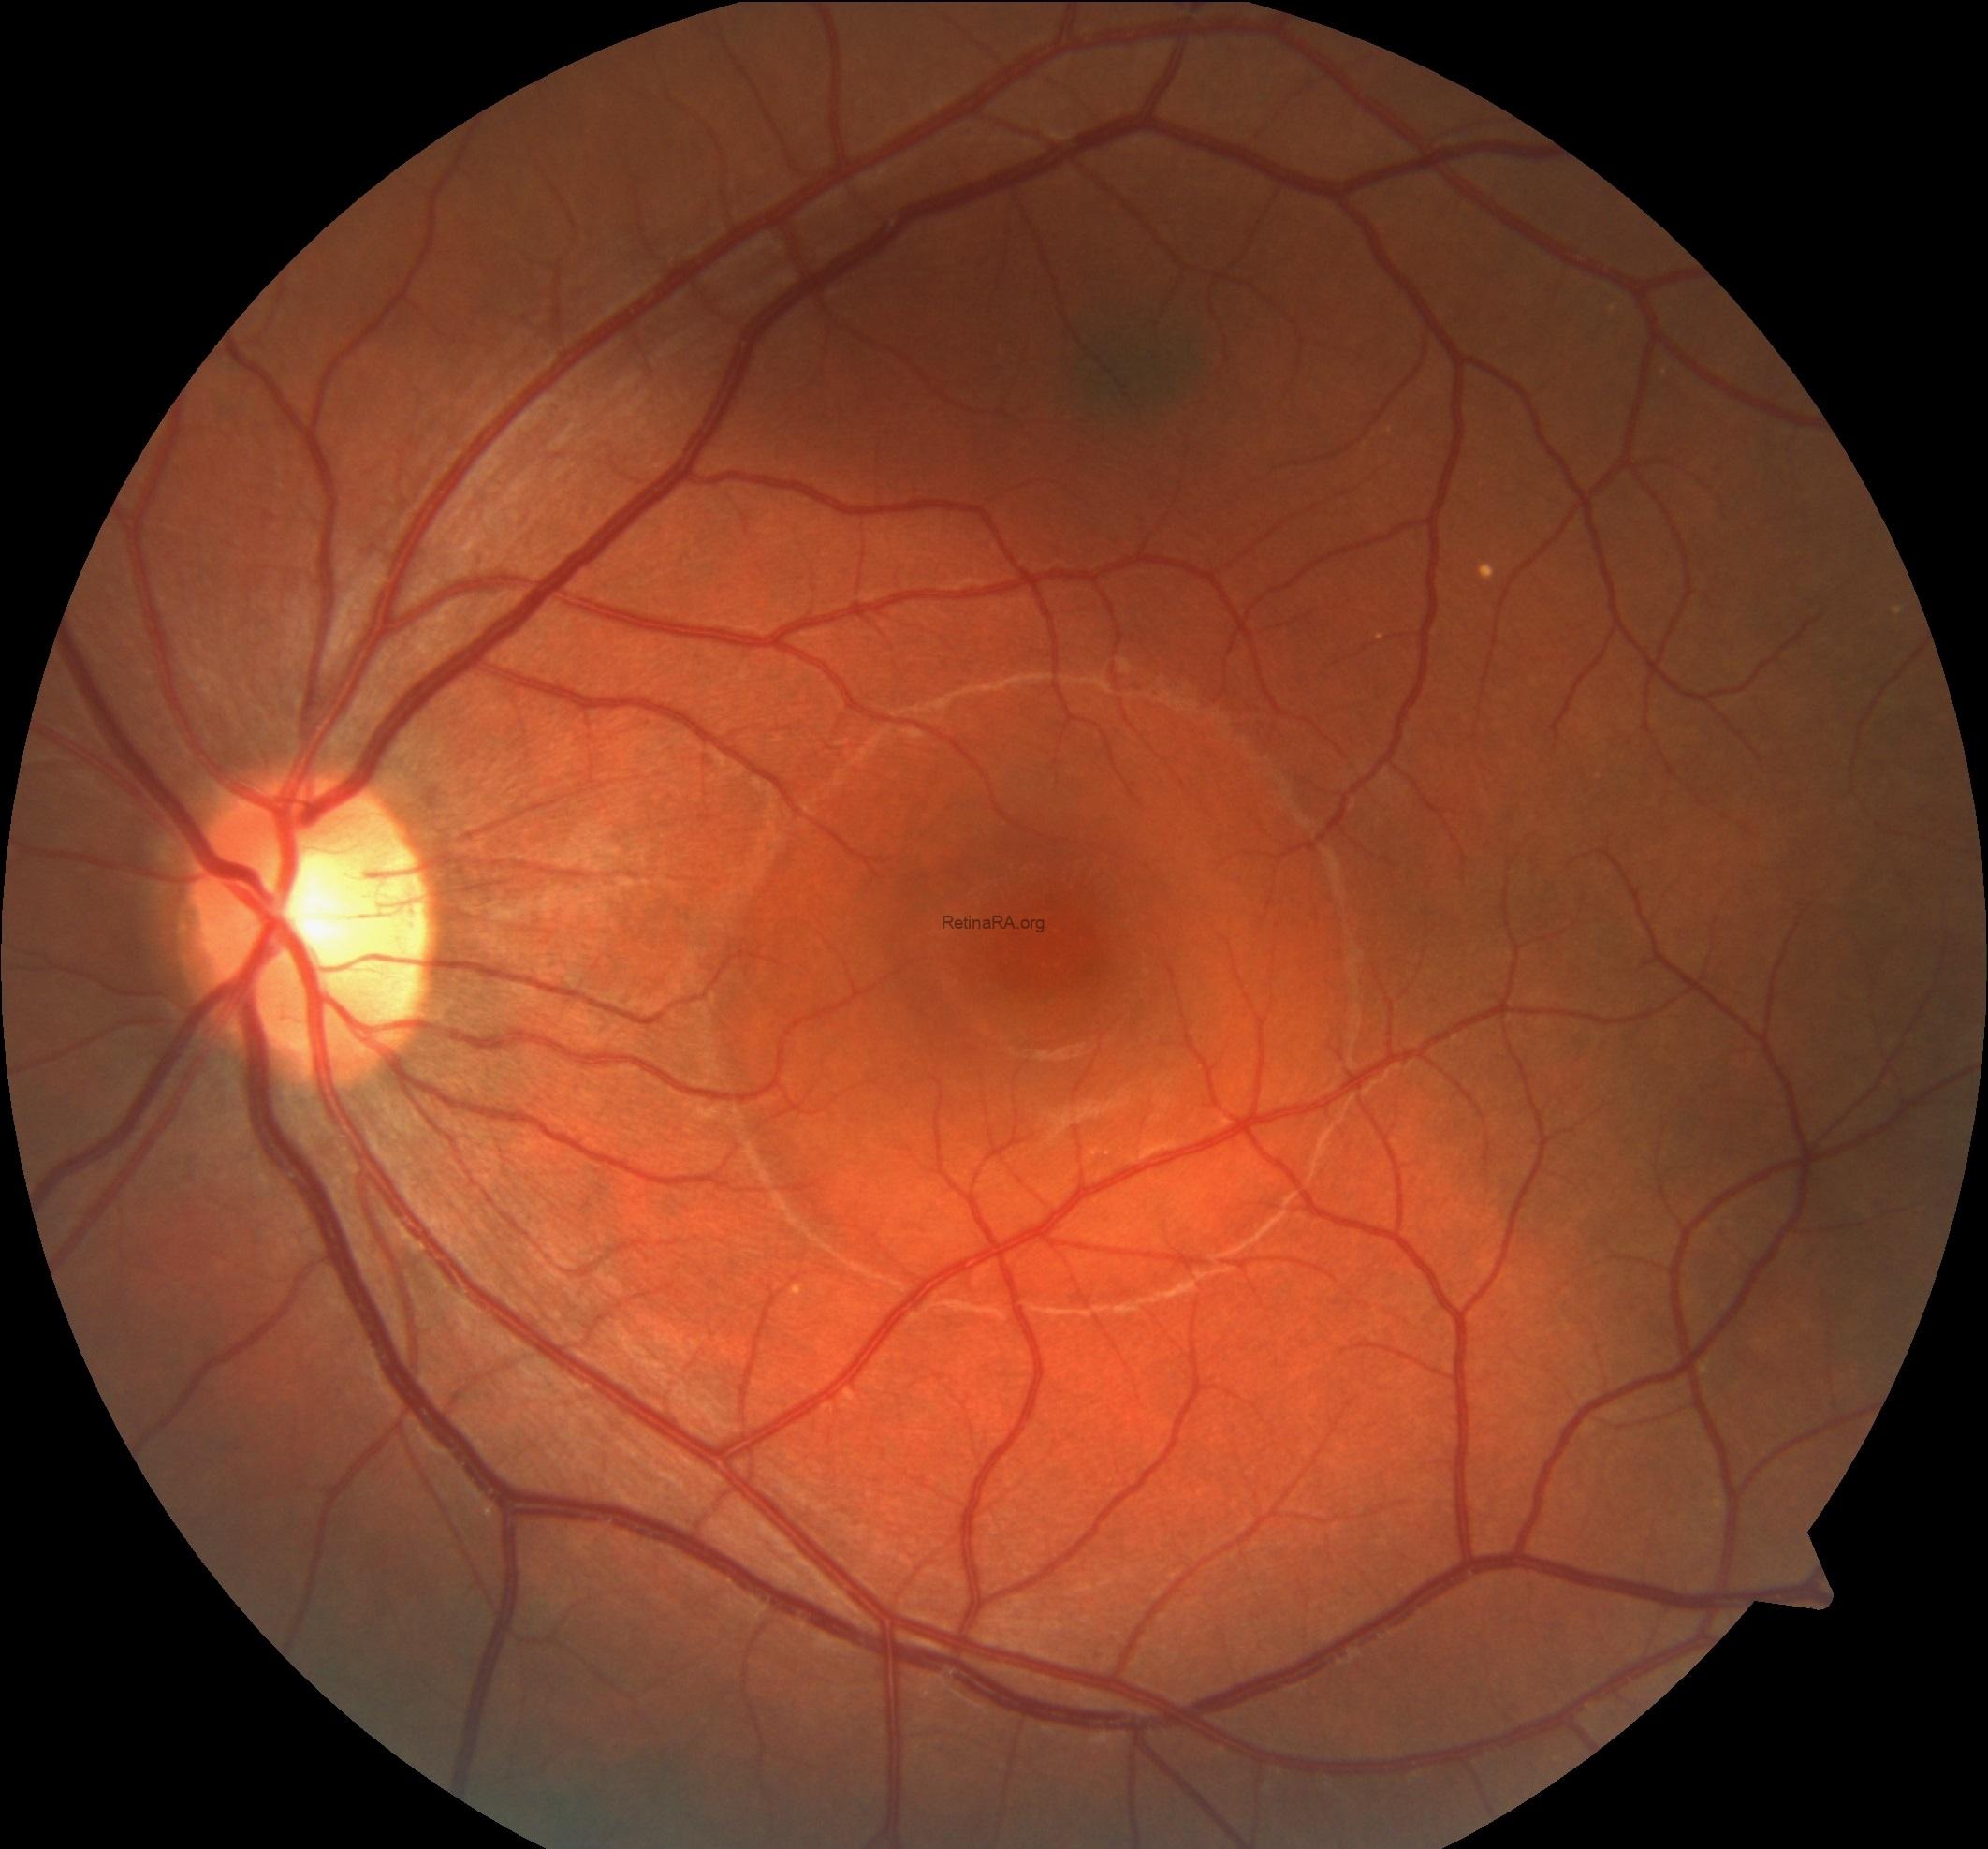

Fundus images of the left eye showed the abnormal foveal reflex with an area of retinal elevation consistent with subretinal fluid in the central retina. Additionally, a choroidal nevus located superior of the fovea was also noted. The right was completely normal.